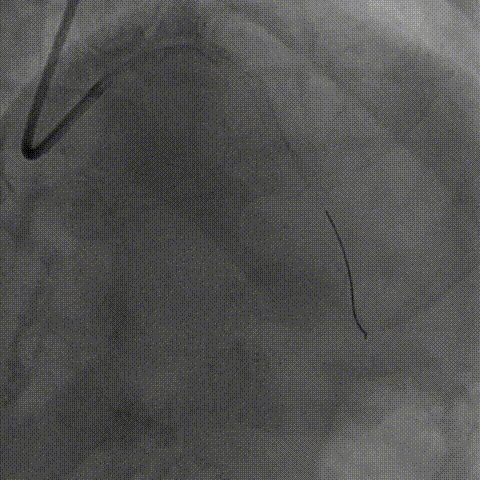

对LAD近段-LM 进行IVUS检查,提示重度钙化病变

针对LAD近段-LM 选择shockwave3.5*12mm,间断触发脉冲,每5个脉冲为一组,只4atm治疗,省略6atm扩张,每次回撤Guiding,共8个周期;

LAD开口前后IVUS

LM前后IVUS

选择shockwave3.0x12mm于LCX近段-LM ,间断触发,8个周期

LCX开口前后IVUS